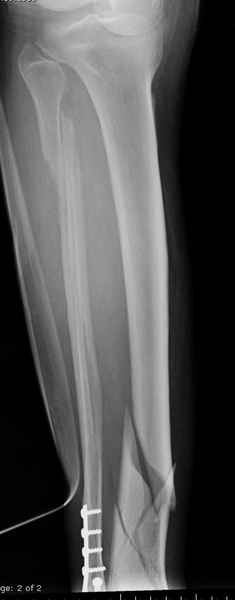

У меня молодой врач на линии, снимки отправил через эл. почту,

спрашивает что делать с больным который поступил недавно, фермер 55 лет падение при пьяной драке в баре, года два назад перенес операцию на лодыжке, на снимках и КТ перелом без вовлечения сустава,

Повреждение такой локализации, на которой применимы и аппарат (классический Илизарова или гибридный), пластина, особенно Locked Plate, и гвоздь с блокированием. В нашей клинике был бы выполнен закрытый интрамедуллярный остеосинтез. Желательно использовать гвоздь с возможностью провести более чем 2 обычных фронтальных винта в дистальном отломке.